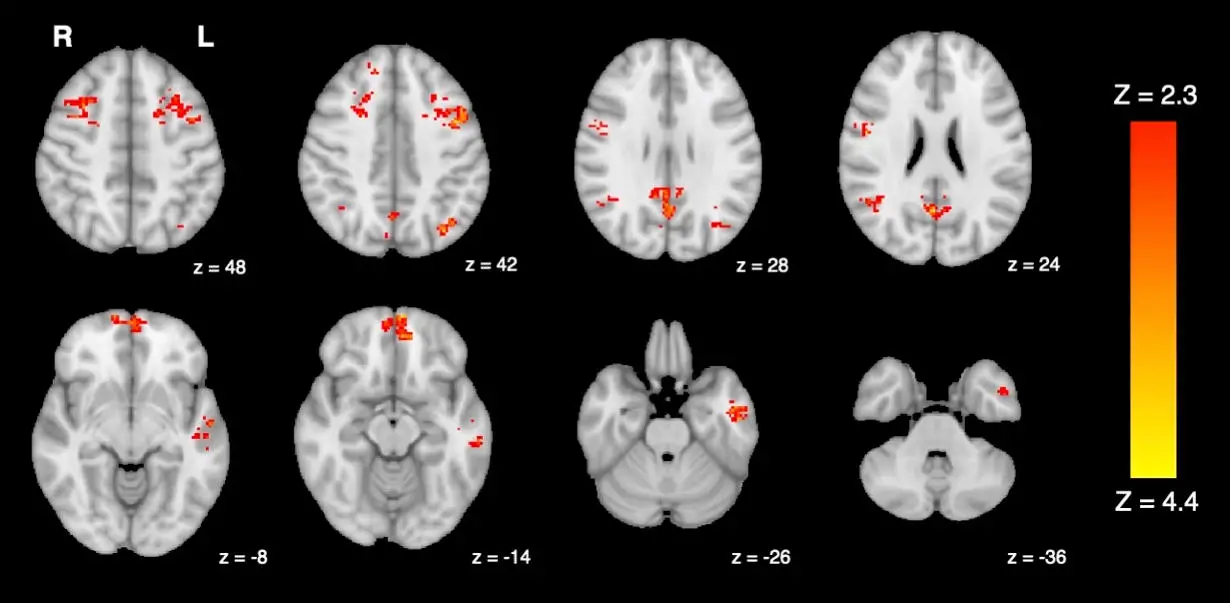

在这项研究中,研究人员在实验室环境中,在不同时间将25名健康成年人短暂地暴露在柴油机废气和过滤空气中,在每次暴露之前和之后,用功能磁共振成像(fMRI)测量大脑活动。

研究人员分析了大脑默认模式网络(DMN)的变化,这是一组相互连接的大脑区域,在记忆和内部思维中发挥着重要作用。fMRI显示,与过滤空气相比,参与者在暴露于柴油废气后,DMN的广泛区域的功能连接性下降。